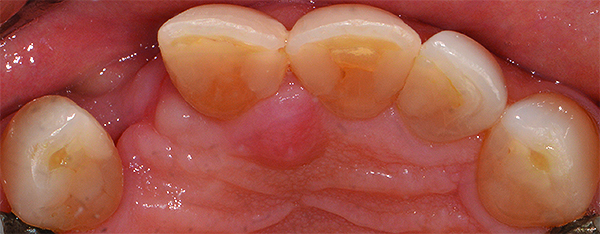

(2.) A patient presented with a missing lateral incisor. The patient was treatment planned to receive a fixed dental prosthesis retained by the adjacent central incisor and canine.

Figure 2

Based on the virtual plan, the treatment is carried out. An example of virtually planned and executed treatment is shown in Figure 2 through Figure 7. The patient presented with a missing maxillary right lateral incisor (Figure 2). Based on the patient’s desires, expectations, and comprehensive examination, a lithium disilicate fixed dental prosthesis (FDP) was planned to restore the missing lateral incisor. A virtual mock-up of the desired treatment plan was performed to delineate tooth length, width, and emergence profile (Figure 3). The treatment plan was then executed by preparing the abutment teeth to receive the FDP (Figure 4). An optical impression was made of the preparations and opposing teeth, and the resulting scans were virtually articulated (Figure 5). The optical impression was used to evaluate all aspects of the preparation, including finish line width and finish, path of insertion, and occlusal and axial reduction. It was also examined for the presence of undercuts, which were delineated by a red color (Figure 6). Errors in preparation design can be easily corrected and a new optical impression of the modified areas can be made without having the patient return for another visit. Once completed, the digital files can be sent to the laboratory for restoration design and manufacture, or used to design and fabricate the restoration using an in-house milling machine.14 An example of a completed restoration is shown in Figure 7.